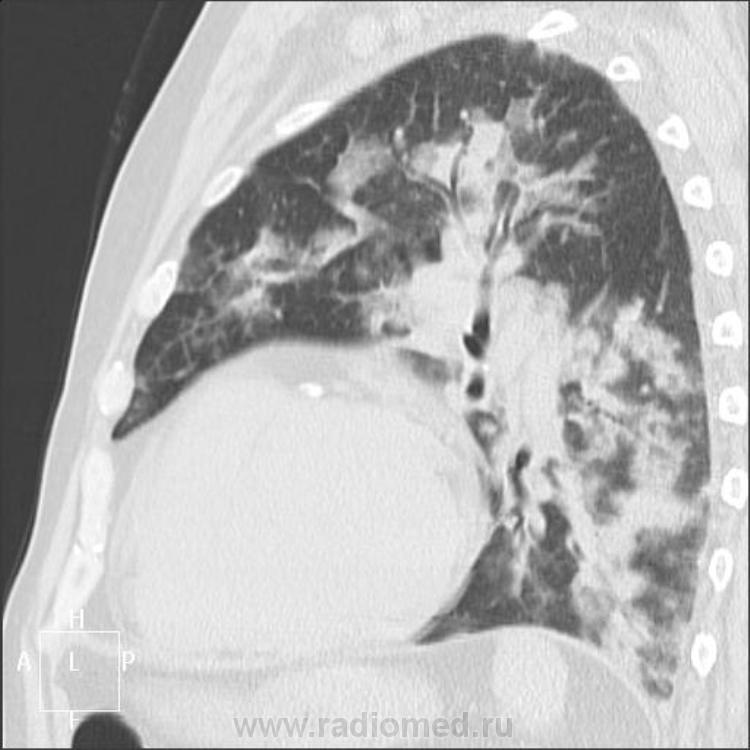

По "скорой помощи" 8.03.2011 поступил пациент 64 лет, инвалидность по хроническому обструктивному бронхиту и ИБС (мерцательная аритмия, стенокардия, постинфарктный кардиосклероз от 2002г). Удушье, кашель малопродуктивный, анасарка. Температура 38,6, в крови незначительный сдвиг формулы влево, лейкоциты 8,7, СОЭ 18, гемоглобин 118 г/л. Обзорный снимок сидя за 8.03 на описание предоставили вчера, заказала оба боковых.

Пациента сегодня в рентгенотделение привезли в кресле, с большим трудом удалось сделать один плохо читаемый боковой (пять снимков, один другого краше, все с динамической нерезкостью, кашель, тремор). С 8 по 11 марта увеличение одышки в покое с 20 до 25 в минуту. Ваше мнение, уважаемые коллеги?

КТ 11.03.2011:

Заинтриговало несоответствие бокового снимка прямому. Тоже первая мысль была, что отек. Хрипы есть дистантные, но жужжащие, сухие. Кашель непереставаемый. Лучше снимков нет. КТ есть.

Потому как не знаю, интерстициальная полисегментарная пневмония или отек легких.

Вновь порадовала Людмила Григорьевна очерствевшие сердца служителей конвенциональной рентгенологии. Всё же хочется не просто радоваться, но и выразить признательность доброй и щедрой Фее нашей. По рентген снимкам и КТ-ушкам, на мой взгляд, получается альвеолярный отёк лёгких. Однако, пневмонию двустороннюю это не исключает. И развиться ей на таком фоне (не забудем и хронический обструктивный бронхит) ничто не мешает. Если пациент проживёт ещё неделю, и за это время Добрые доктора не сумеют выписать его домой, на вскрытии пневмония, думаю, найдётся. Ну, само собой справа выпот плевральный.

Интерстициальная пневмония - по презентации Марио интерстициальных заболеваний легких, похоже. Но и на отек похоже. А КТологи - КТшники молчат...

... Скончался вчера, на секции полисегментарная пневмония, отека нет, гидроторакс справа.

И коллега Helios права по своему: то что мы пишем, действительно, зовётся рентген заключение. Да ведь и коллега Almo употребляет именно слово, «заключение», а не «диагноз». Хотя в диагноз оно порой включается терапевтами слово в слово. И Андрей Юрьевич, конечно, прав: на первом снимке, как утро туманном, картина застоя видна вполне ясно. Застойная пневмония в нижнемедиальных отделах, особенно слева, при наличии достаточного опыта и фантазии угадывается, а вот "малый гидроторакс справа", который Андрей Юрьевич с самого начала предположил, мне моя фантазия не показала. И коллега Almo, разумеется, прав, увидев после относительно спокойной рентгенограммы в прямой проекции от 8 марта, боковую проекцию от 11 марта и КТ с грозными изменениями в верхних долях, ранее невидимыми и я охотно с ним согласился, учитывая такую быструю динамику в лёгких и скорбные дела сердечные. Надо ещё учесть, что мы с ним в КТ-ушках неискушенные. Вот и Людмила Григорьевна к вечеру согласилась: "Интерстициальная пневмония - по презентации Марио интерстициальных заболеваний легких, похоже. Но и на отек похоже". А то, что патологоанатом отёк лёгких на вскрытии не увидел…, так это состояние ИМХО может быть обратимо при успешности соответствующей терапии.